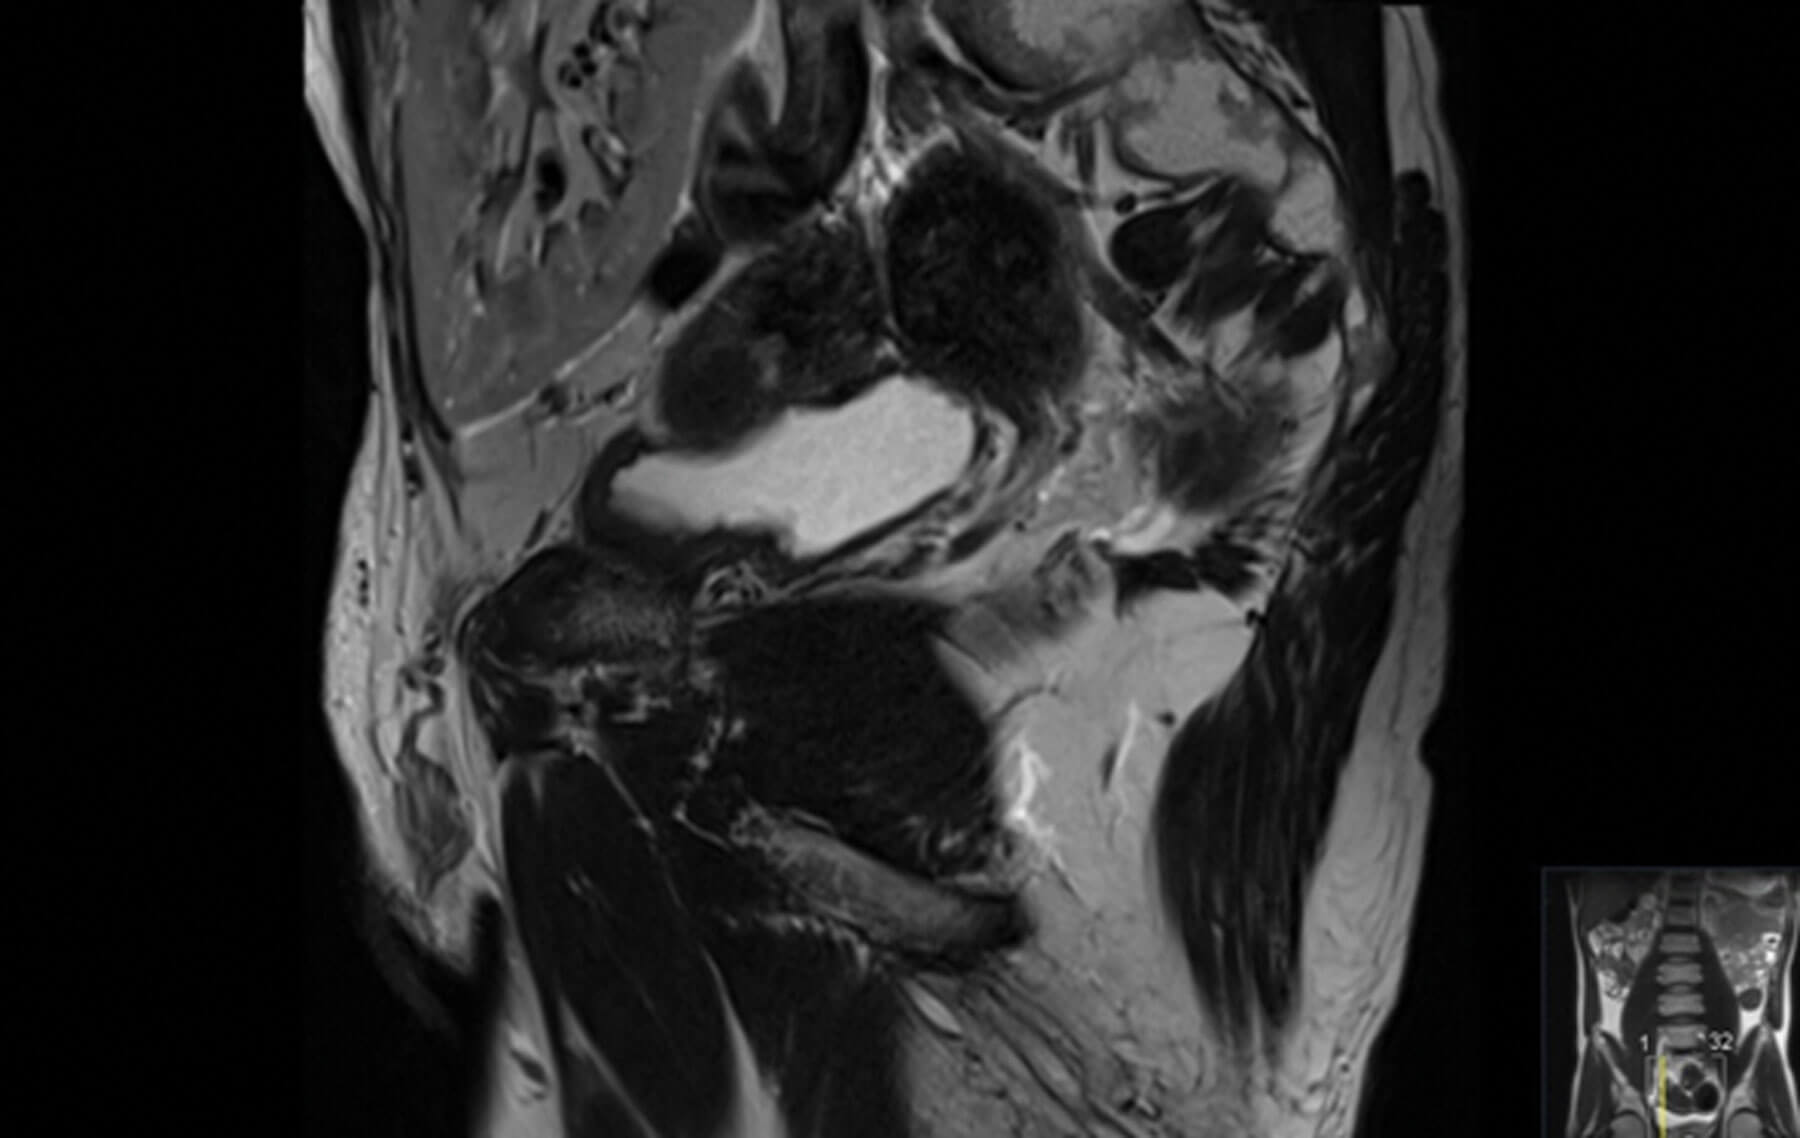

Figure 2: Sagittal image of MRI prostate showing

the proximity of renal transplant to the bladder.

A 55-year-old male had chronic renal failure requiring initial peritoneal dialysis. He had a renal transplant from his partner four years ago. His initial prostate specific antigen (PSA) during the transplant work-up was one. This increased to nine within two years. Another increase in PSA triggered an MRI scan of the prostate which revealed a PI-RADS 5 lesion, T3a in a 20cc prostate. He proceeded to a transperineal prostate biopsy which revealed a Gleason 4+3 cancer with a maximum cancer length of 10mm. Staging prostate specific membrane antigen positron emission tomography (PSMA PET) scan showed no nodal or distant metastasis. He is on regular tacrolimus, anti-hypertensive and insulin. He has a functioning renal transplant.

Any treatment for prostate cancer in renal transplant recipients poses a few difficulties. Firstly, we have to avoid direct or indirect injury to the anatomical location of the transplanted kidney which may occur from surgery or from radiation. We have to also consider the effect of peritoneal dialysis or adhesions and the potential need for further transplants in case of graft failure.